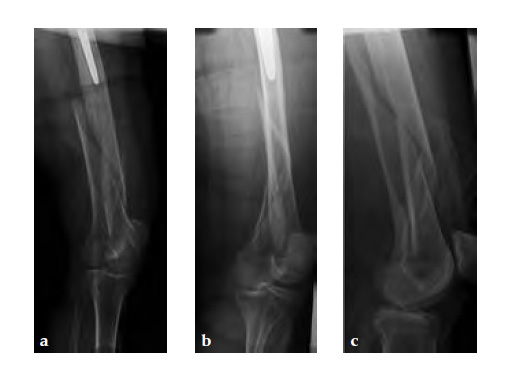

Case 2: A 76-year-old female with a Vancouver type C fracture.